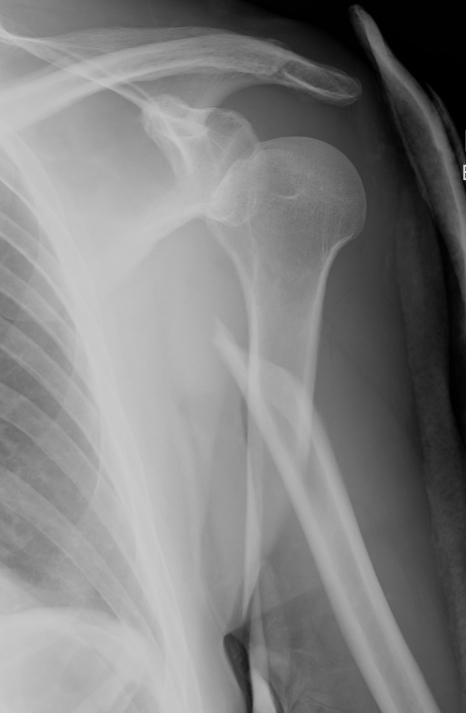

Displaced Humeral Fracture APDisplaced Humeral Fracture Lateral

Proximal fracture

Prox humerus 1Prox humerus 2Prox humerus ORIFProximal humerus ORIF

Proximal third humerus ORIF of nonunion